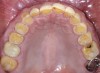

Fig 20. Postoperative occlusal view of maxillary arch with full-contour monolithic high-translucent zirconia restorations on all teeth.

Figure 20

A 40-year-old patient presented with the chief complaint: “My teeth are cracking, and I would like to have my original bite.” Dental findings included Class I occlusion with slight misalignment between teeth Nos. 8 and 9. Generalized severe occlusal wear and slight Class I mobility of teeth Nos. 23 to 26 were noted. Caries lesions were found on teeth Nos. 2, 4, 6, 8, 9, and 14 and abfraction lesions on teeth Nos. 4, 5, 10, 11, 13, 20, and 21. Figure 1 through Figure 3 depict the preoperative situation. Full-mouth rehabilitation was suggested. The goals for the restorative treatment were management of erosive etiology, conservation of tooth structure, and long-term protection of the restorations. A diagnostic wax-up was instrumental in determining functional and esthetic treatment goals and establishing new anterior guidance (Figure 4). A comprehensive, step-by-step treatment approach was applied, which, after periodontal pretreatment, caries control, and provisionalization, included definitive preparation (Figure 5) and restoration of the maxillary anterior teeth to establish anterior occlusal guidance. CAD/CAM–fabricated full-contour monolithic high-translucent zirconia crowns (Katana™ UTML Ultra Translucent Multi-Layered, Kuraray Noritake Dental, kuraraynoritake.com) were fabricated (Figure 6 and Figure 7) and cemented with self-adhesive resin cement (Panavia SA, Kuraray Noritake Dental). Figure 8 demonstrates the cemented anterior crowns and refined conservative preparations of posterior teeth, which were performed with minimal tooth-structure removal. High-translucent monolithic zirconia onlays and crowns were fabricated (Katana Zirconia UT, Kuraray Noritake Dental) (Figure 9 to Figure 12). The posterior restorations were adhesively bonded following the APC zirconia-bonding concept. APC-Step A involved air-particle abrasion with 50-μm aluminum oxide at 1.5 bar with a chairside microetcher (Figure 13), followed by application (APC-Step P, Figure 14) of a special ceramic primer (ClearfilTM Ceramic Primer, Kuraray Noritake) with adhesive phosophate monomers (MDP). Relative moisture and contamination control was achieved with cotton rolls and retraction cords. Rubber dam placement, which is always preferred, was difficult in this situation. The enamel surfaces of the abutment teeth were selectively etched (Figure 15) with 35% phosphoric acid (K-Etchant Gel, Kuraray Noritake Dental) and the dentin conditioned (Figure 16) with a self-etch dentin primer (Panavia V5 Tooth Primer, Kuraray Noritake Dental). A dual-cure adhesive resin (Panavia V5 Paste Universal, Kuraray Noritake Dental) was dispensed directly into the restorations with an automix syringe. The restorations were inserted, and excess cement was carefully removed (Figure 17 and Figure 18) before light polymerization (Figure 19). Postoperative views depict the treatment outcome (Figure 20 to Figure 22).